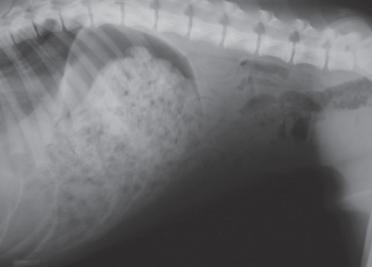

后续体格检查,体温38°C,呼吸55次/min,仔细观察腿部并未发现异常,但呼吸明显急促,需进一步影像学检查才知道结果。X光片结果显示肺部显影明显异常,结合上述情况后,确诊为创伤性膈疝,应立即开始膈疝修复手术。

右侧腹部X光片

X光可显示肺部显影是否异常,肺部区域有没有被压迫的情况。